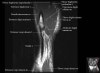

- Sagittal section

Sagittal T1 evaluates the tendons, bone marrow and relationships between the osseous structures.